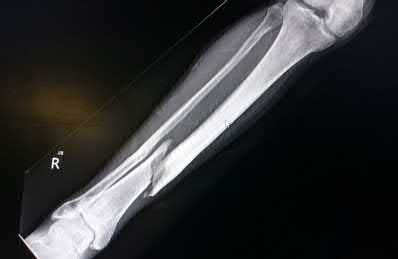

A 28-year-old male sustains a closed comminuted tibial shaft fracture.

Two hours post-injury, he develops severe leg pain unyielding to narcotics. His blood pressure is 120/80 mmHg. Intracompartmental pressure monitoring is performed. Based on current guidelines, which measurement dictates an emergent 4-compartment fasciotomy?